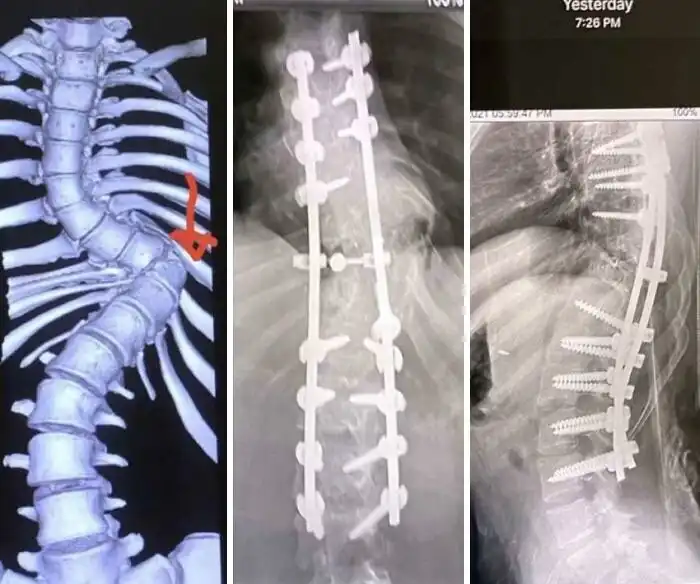

10. Последствия выстрела в локоть из дробовика 12-го калибра на рентгеновском снимке

11. "У моего приятеля сколиоз, это фото с его операции"